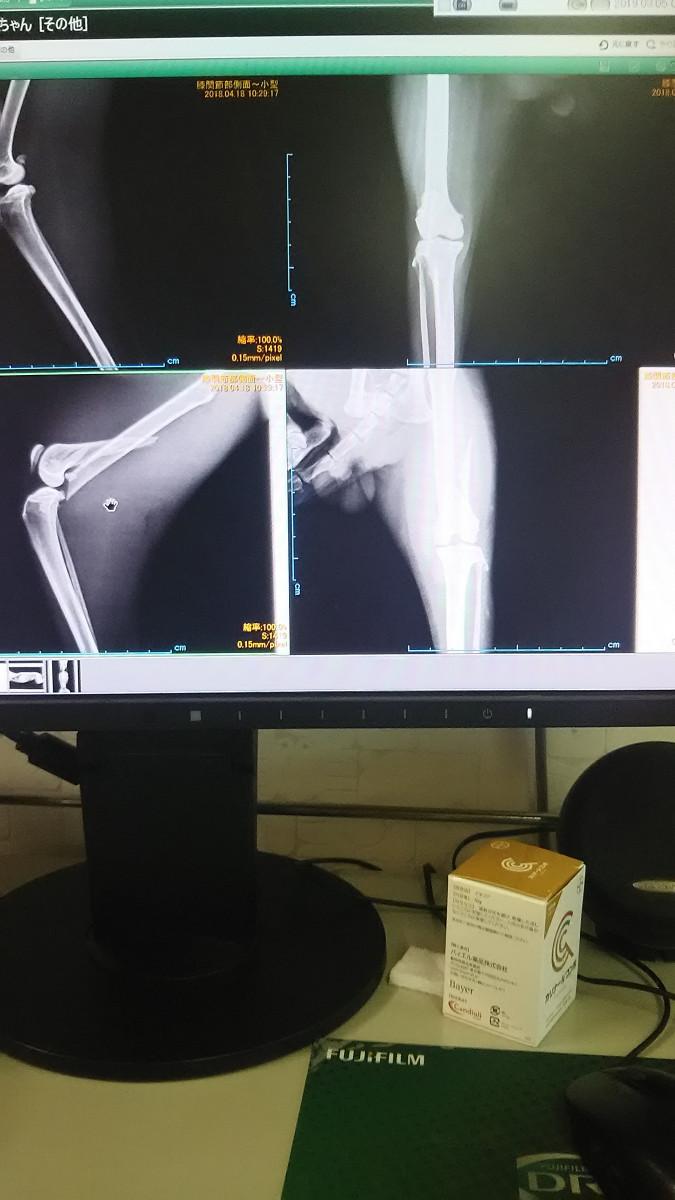

ちなみにこれが骨折直後のレントゲン

下段の2枚が折れた骨

今はプレートとボルトで固定して

ちゃんとくっついてます☺